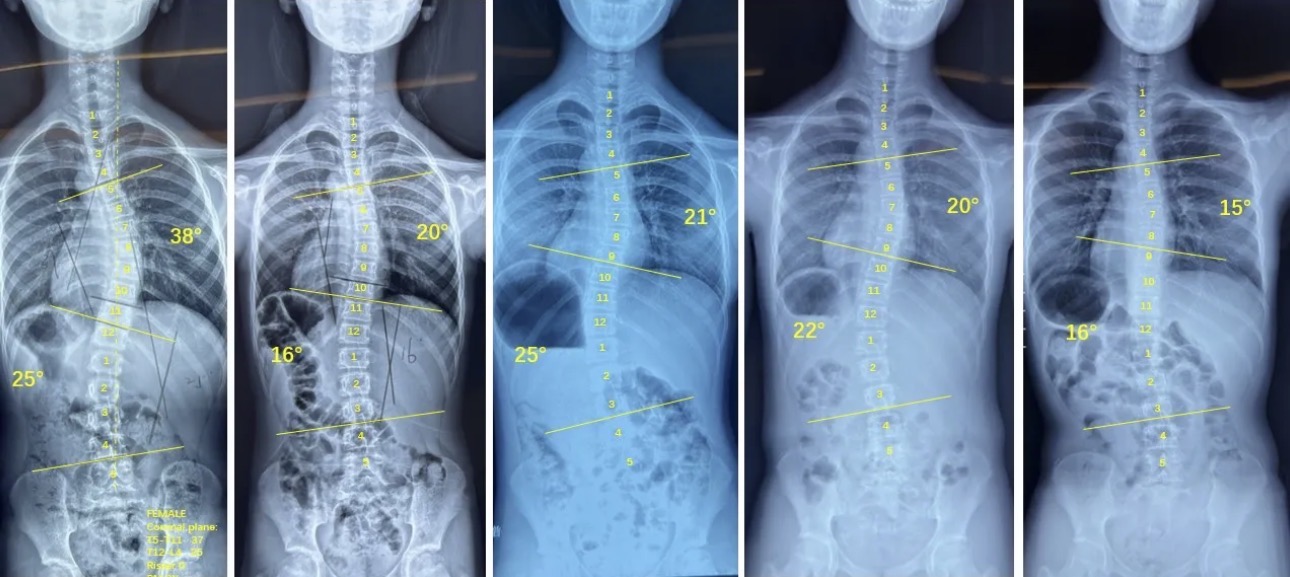

衷德脊柱,我们只关注侧弯保守治疗~

Zhongde Spine, bending no breaking ~